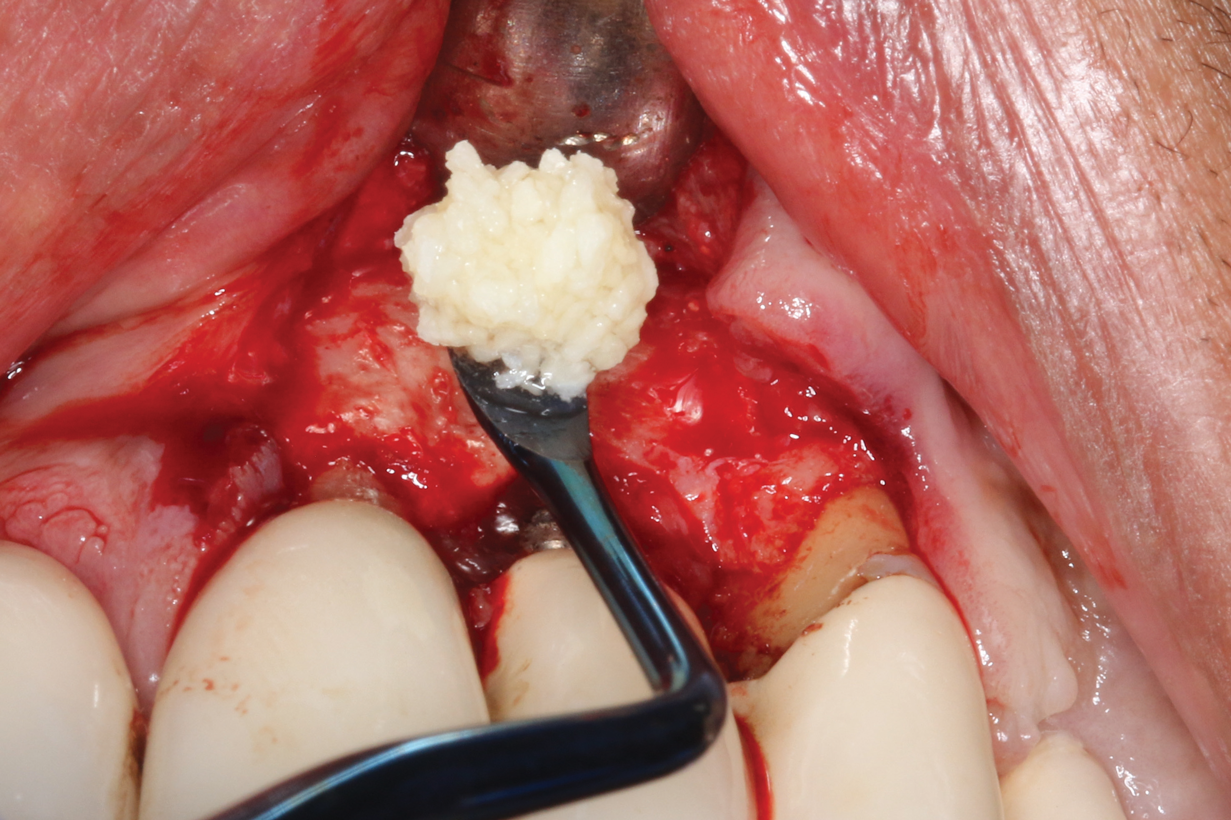

There are many grafting materials available today, including allografts (from a human source), xenografts (from another species), and alloplasts (from synthetic materials).23 Following debridement and sterilization of the apical lesion, the site was grafted with a mineralized cortical/cancellous bone allograft material (Newport Biologics Mineralized Cortico/Cancellous Allograft Blend, Glidewell Direct [alternatively: OSSIF-I sem Mineralized Cortical/Cancellous Bone Allograft, Surgical Esthetics; enCore® 50/50 Cortical & Cancellous Allograft, Osteogenics]). The material was packed firmly around the entire implant body but not crushed (Figure 7). Next, a resorbable collagen membrane (Newport Biologics Resorbable Collagen Membrane 3-4, Glidewell Direct [alternatively: Bio-Gide®, Geistlich Biomaterials; BioMend®, Zimmer Biomet]) was trimmed to extend approximately 2-mm beyond the borders of the defect and then passively positioned to serve as a barrier against epithelial growth during the healing and remodeling phase (Figure 8). A sling suture technique using polyglactin 910 suture was then used to reposition the envelope reflection (Figure 9 through Figure 11). Polyglactin 910 suture is a smooth, synthetic, absorbable, braided suture made of polyglycolic acid that is broken down over time by hydrolysis. This suture material reduces the inflammatory response that can be observed with other suture materials.

(7.) Allograft was firmly packed around the implant body without crushing the material.

Figure 7